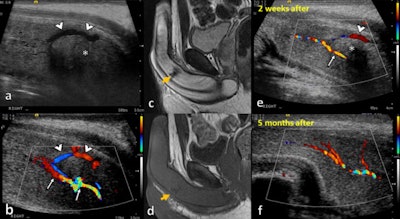

"CEUS may help to delineate both cavernosal and extratunical hematomas, as they do not enhance after microbubble injection," explained Gómez-Bermejo and colleagues in an e-poster that received a cum laude award at ECR 2023. "CEUS improves the localization of tears of the tunica albuginea and could help to differentiate cavernosal tissue herniation from hematoma, as the former enhances."

Also, CEUS can increase the operators' confidence in confirming vessel patency and demonstrating active bleeding and pseudoaneurysms, and it can help to locate a dislocated penis and assess its viability.

Cavernosal hematomas usually result from injury to the subtunical venous plexus or smooth-muscle trabecula secondary to compression of the penis shaft against the pelvic bones, and they are often bilateral and can be associated with penile fractures and arterial injuries with high-flow priapism, the authors wrote.

Extratunical hematomas can be superficial or deep to the Buck fascia, depending on the site of involvement of the penile veins, and they can be associated with an arterial lesion (such as an arteriovenous fistula) or thrombosis of the superficial and deep dorsal penis veins.

"The B-mode appearance of a penile hematoma can vary with its age, being hyperechoic in the acute phase and cystic with septations in chronic stages. In the long-term, fibrosis can be developed, appearing as an ill-defined echogenic abnormality," the authors noted, adding that on CEUS, a penile hematoma appears as a non-enhancing area, and it allows a confident diagnosis and a better delineation of the hematoma.